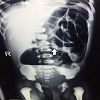

Case presentation: A 1-day-old male baby presented to the emergency room with marked abdominal distension and absent anal opening. On exploration, the baby was found to have CPC (Type 2) with colonic atresia. This association has not been reported in English literature.

Conclusion: This is a report of a case of type 2 CPC with colonic atresia. To the best of our knowledge, such an association has not been reported so far. The final embryological outcome is dictated both by the topography and timing of vascular insult.

Mathur M, Saxena A, Bajaj M, Chandra T, Sharma N, Simlot A, et al. Role of plain abdominal radiographs in predicting type of congenital pouch colon. Pediatr Radiol. 2010; 40:1603–8.